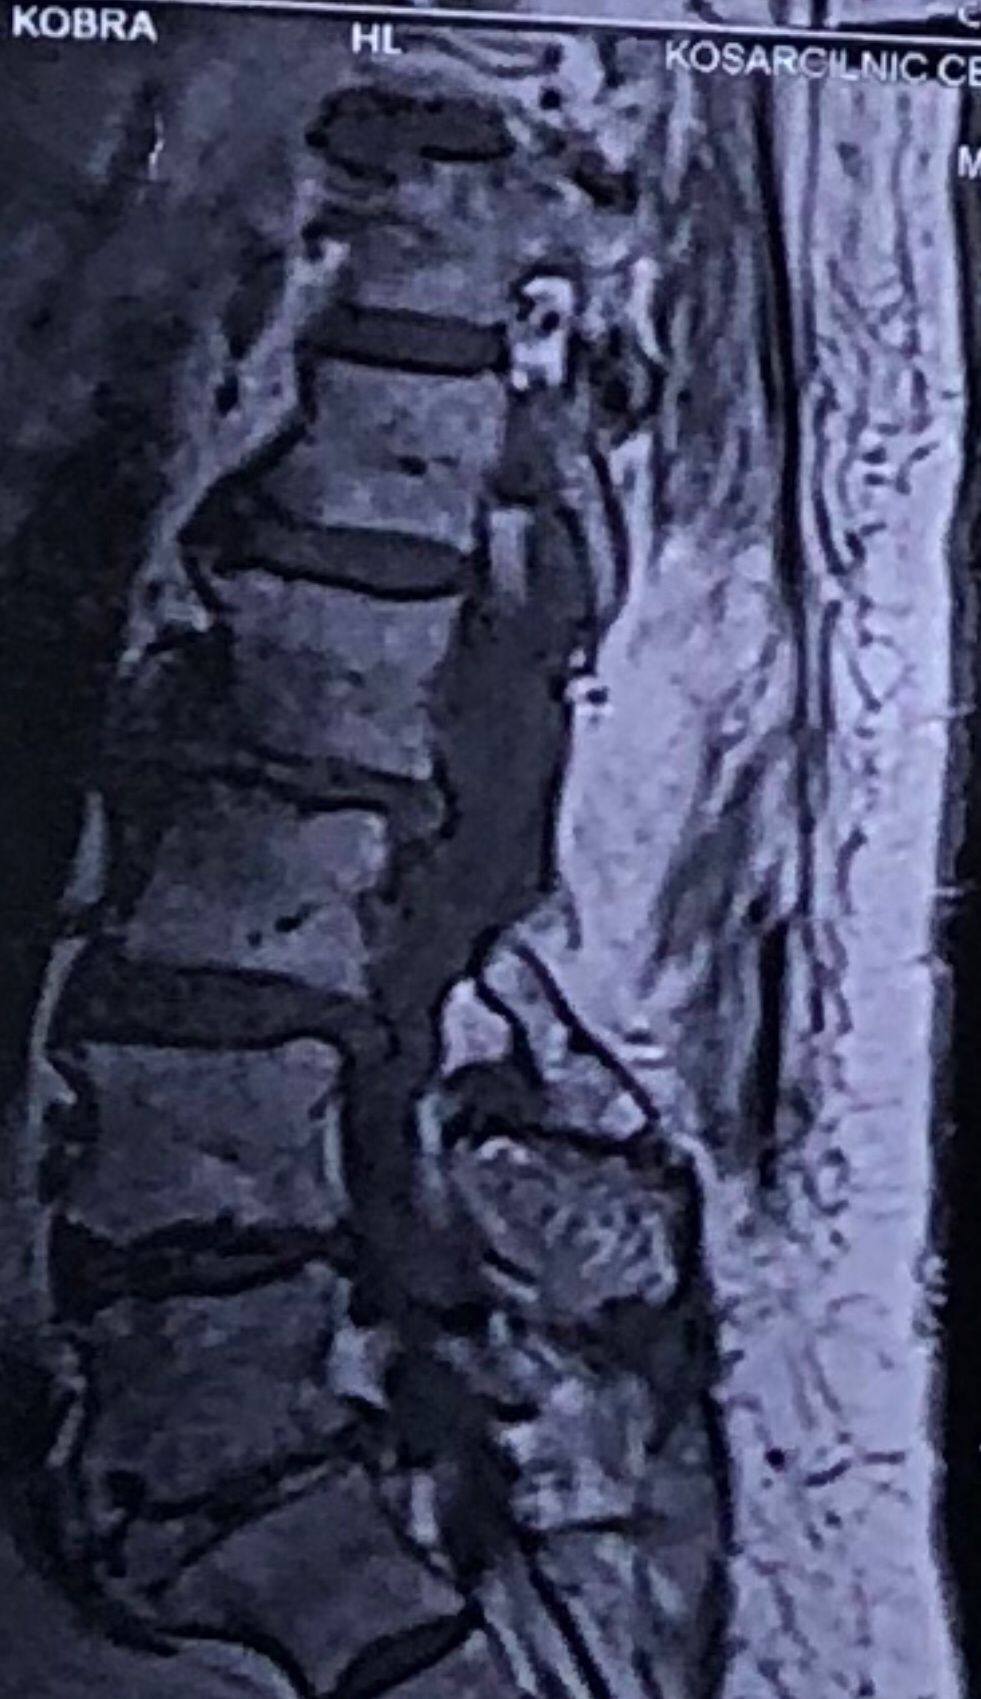

46 years old female patient presented to my clinic yesterday june 1/2025 with LBP and radicular L leg pain for several months which hasn’t responded to physio 2 neurosurgeons have visited her and didn’t suggest any surgery Neurological exam was unremarkable please see her mri/ emg/ncv and her huge tarlov cyst and possible L IVF L4-5 hyperbulge I ordered sacrum mri and ct scan and new emg/ncv and asked her with her sacral Ct scan and MRI first sees another two famous neurosurgeons and see if that large cyst is the reason for her pain if not i can work on her L4-S1 area Do you think her radicular pain can originate from her large cyst in sacrum? Do you consider surgery and removing her sacral cyst?